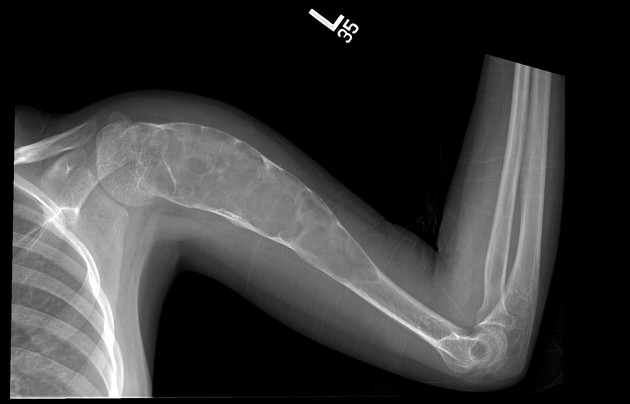

Kista Tulang Sederhana (Simple Bone Cyst/SBC), juga dikenal sebagai kista tulang unikameral (unicameral bone cyst/UBC), merupakan lesi soliter berisi cairan yang dapat memiliki satu ruang atau bersepta. Kista ini paling sering ditemukan di humerus proksimal (tulang lengan atas) dan femur proksimal (tulang paha). Cairan di dalam kista biasanya berwarna kuning jernih dan mengandung berbagai mediator inflamasi (Restrepo et al., 2022).

Evaluasi awal kedua jenis kista tulang dimulai dengan foto polos (radiograph). Pada kista tulang sederhana, gambaran khas berupa lesi litik berbatas tegas dengan tepi sklerotik tipis yang terletak di sentral metafisis tulang panjang. Tanda karakteristik yang dapat ditemukan adalah “fallen fragment sign” di mana fragmen tulang yang patah jatuh ke dasar kista berisi cairan.

Kista tulang aneurismal menampilkan gambaran lesi litik ekspansif dengan penipisan korteks yang memberikan tampilan “seperti balon” (balloon-like appearance). Lesi yang lebih besar dapat tampak bersepta. Pada MRI, gambaran paling khas adalah adanya level cairan-cairan (fluid-fluid levels) yang mencerminkan sedimentasi komponen darah di dalam rongga kista (Restrepo et al., 2022; Alston et al., 2025).